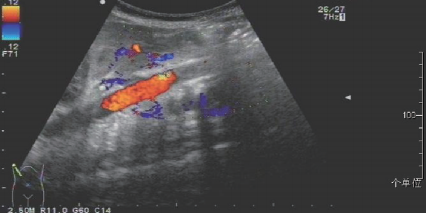

入院诊断:新生儿缺氧缺血性脑病、胎粪吸入性肺炎、新生儿低血糖症、巨大儿。患儿入院后予苯巴比妥止惊、抗感染、营养心肌、营养神经等对症支持治疗。入院第3天患儿抽搐止,双上肢肢端肤色红润、皮温正常、CRT正常,双下肢肢端肤色苍白、皮温低、CRT 延长,双上肢血压高于双下肢,血压差异超过 20 mmHg。予行心脏彩超查:左、右室心肌肥厚, 左室流出道梗阻, 卵圆孔未闭。 腹主动脉超声检查:腹主动脉近肾动脉水平内可见实质性低回声充填,内未见明显血流信号,双侧髂外动脉血流速度约15cm/s, 呈阻塞性频谱。进一步头颅及腹部增强 CT 示: 头颅未见明显异常;左肾动脉平面以下腹主动脉、髂总动脉未见显影,考虑为动脉栓塞可能;主动脉弓远端轻度缩窄;主动脉弓远端囊样突出,不除外弓动脉残留并附壁血栓形成;室间隔及左右室壁心肌肥厚;左肾血灌注减低,不除外左肾动脉受累狭窄。